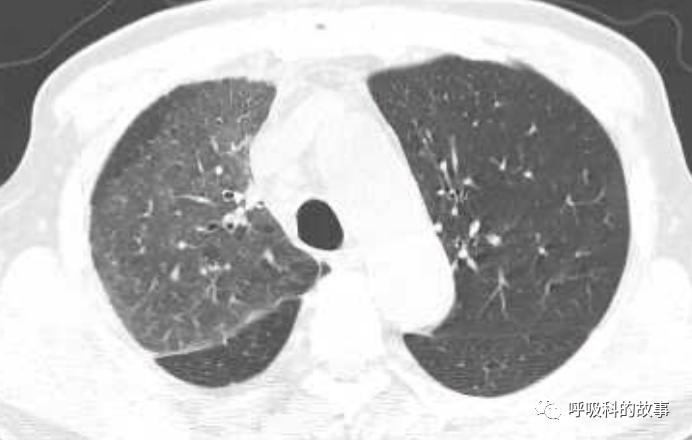

所以如果我们能对这些特征有所了解,那么其实诊断肺马尔尼菲蓝状菌感染并不是什么难事。后来我们又遇到一个肺部结节的患者(如下图):

大家可以发现这个小结节外周有晕征,内部有一小空洞,更重要的是纵隔淋巴结肿大,因此我们马上考虑到肺马尔尼菲蓝状菌感染,进行气管镜检查,做纵隔淋巴结穿刺培养出马尔尼菲蓝状菌。